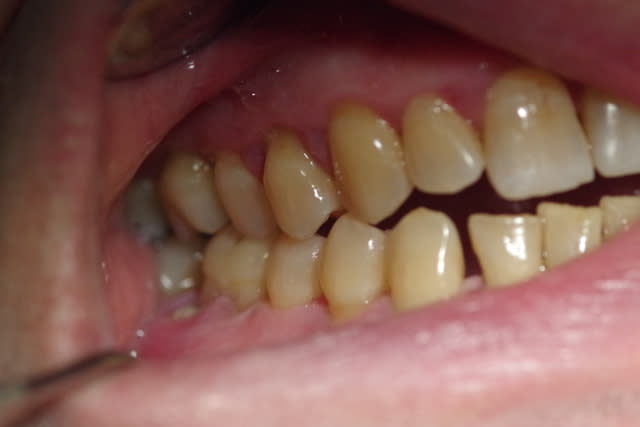

Le patient de 65 ans n'a plus d'occlusion sur le secteur ant et sur le secteur postérieur gauche.

L'occlusion ne se fait que sur les 5, 6 et 7 côté droit.

PS2 Les dents, sur les secteurs postérieurs, se sont considérablement écartées sans doute due à la pulsion linguale.

J’ai mis des photos des modèles qui n’arrivent pas bien sur à être en occlusion.

Le patient occluse uniquement côté droit au niveau prémolaire et molaire.

Je me suis amusé aussi à mettre en occlusion les modèles côté G ( comme on voit sur une photo) et bien évidemment le côté droit était en inocclusion.